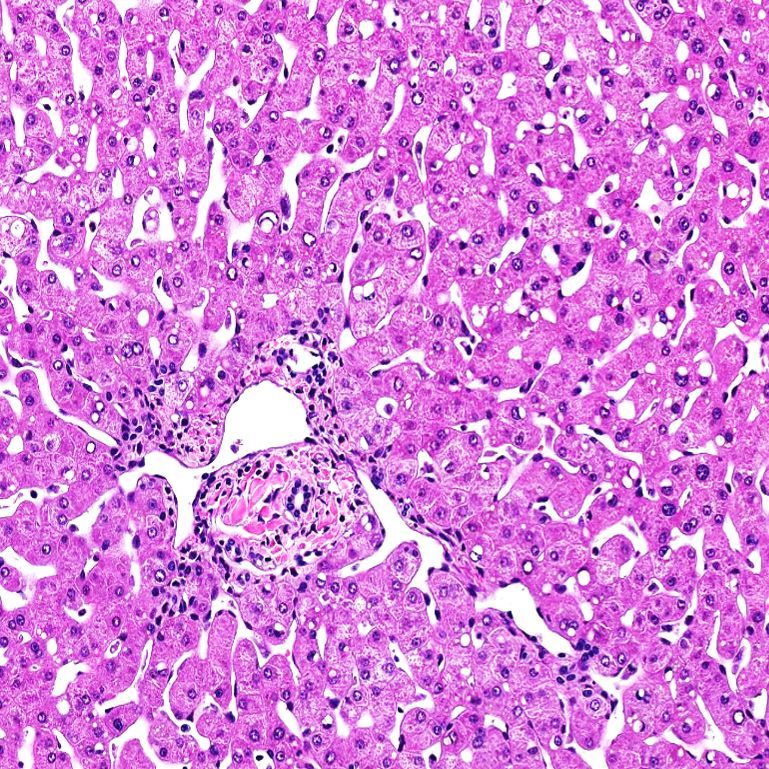

提供健康与病变组织样本,详细的供体病史和病理报告、病理诊断(包括炎症和纤维化评分)以及相应的H&E和三色图像。

速冻组织(SFT)样本涵盖了 0-6 级的非酒精性脂肪肝 / 非酒精性脂肪性肝炎(NAFLD/NASH)谱系。每个样本均包含完整的捐赠者医疗及社会史报告,以及详细的组织病理学评估,包括非酒精性脂肪肝活动度评分(NAS)和纤维化分期。

福尔马林固定石蜡包埋组织样本( FFPE )

LifeNet Health 提供一系列非酒精性脂肪肝 / 非酒精性脂肪性肝炎(NAFLD/NASH)捐赠者的人肝组织福尔马林固定石蜡包埋块。